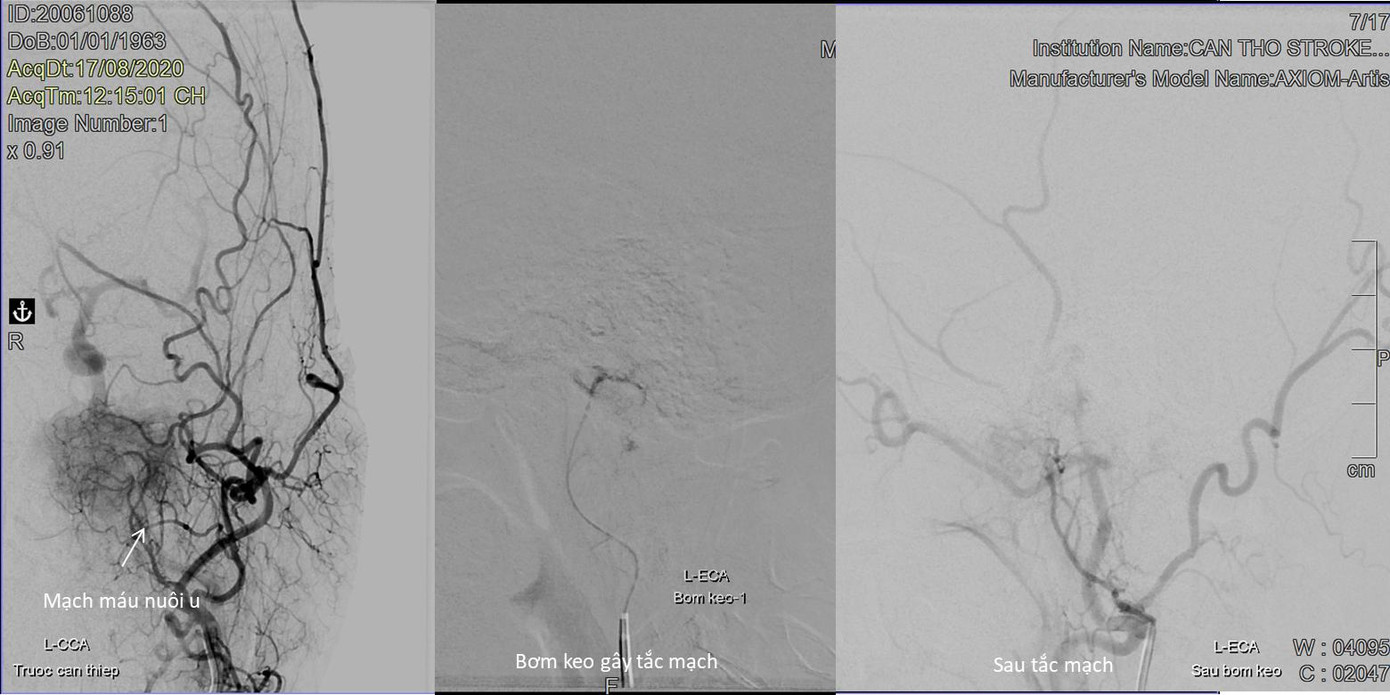

Trước đây, việc điều trị u màng não vùng mặt dốc xương đá nói riêng và các U màng não nói chung phương pháp điều trị thường gặp nhất là xạ trị hoặc phẫu thuật.

Tuy nhiên, tỷ lệ tử vong cũng như biến chứng sau mổ là rất cao: bệnh nhân có thể bị liệt nửa người hoặc tổn thương các dây thần kinh sọ gây liệt mặt (dây VII), giảm khả năng linh hoạt của mắt, sụp mí (dây III)... Y học càng tiến bộ, thiết bị chẩn đoán và phương pháp điều trị ngày một phát triển, vì thế các bệnh lý mạch máu có thể điều trị thuận tiện hơn bằng phương pháp can thiệp nội mạch.

TS.BS Trần Chí Cường - Giám đốc Bệnh viện S.I.S Cần Thơ chia sẻ: “Thời điểm hiện tại, phương pháp điều trị cho bệnh nhân có U não ở vị trí sâu không thể phẫu thuật, hay có nhiều mạch máu nuôi chính là can thiệp nội mạch gây tắc mạch nuôi u trước mổ giúp cuộc mổ lấy u an toàn hơn hay việc gây tắc mạch nuôi sẽ làm khối u chậm phát triển, thậm chí nhỏ lại. Đây là phương pháp ít xâm lấn, an toàn cao thậm chí không cần phải gây mê trong lúc làm thủ thuật, thường chỉ sau 2-3 ngày bệnh nhân sẽ được xuất viện không để lại sẹo vết trên đầu, không để lại di chứng tổn thương não”.